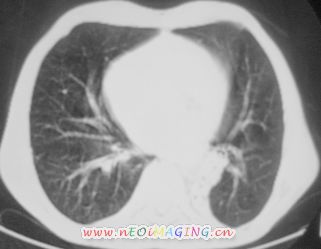

以下是引用南沙在2007-10-7 10:44:00的发言:[br]左下肺不张.[br]肺癌可能性大?

以下是引用卜一在2007-10-7 9:38:00的发言:[br]左下肺胸膜下团片影,内见含气支气管像,临近胸膜未见增厚。多考虑:1 左下肺炎症,建议消炎后复查!2 不除外肺隔离症合并感染!